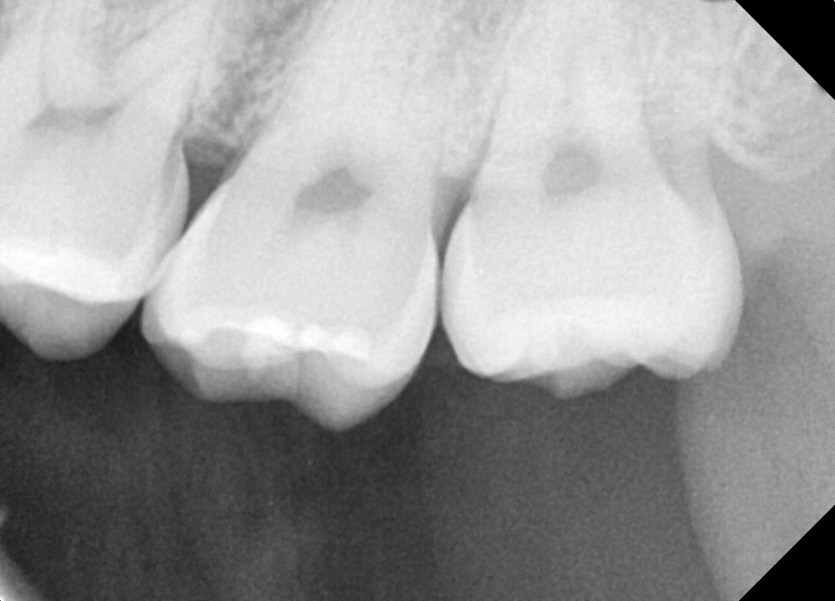

#28,38 사랑니 발치

구강외과 전문의가 당일 발치했습니다.